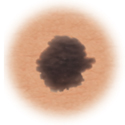

Moles (nevi)

Small skin marks caused by pigment-producing cells in the skin. Moles can be flat or raised, smooth or rough, and some contain hair. Most moles are dark brown or black, but some are skin-colored or yellowish. Moles can change over time and often respond to hormonal changes.

Most moles are benign and no treatment is needed. Some benign moles may develop into skin cancer (melanoma). See below for signs.

Distinguishing benign moles from melanoma

Certain moles are at higher risk of changing into malignant melanoma, a form of skin cancer. Large moles that are present at birth and atypical moles have a greater chance of becoming cancerous. Finding cancerous skin growths early is important because that’s when treatment is most likely to be effective. Removing the melanoma through surgery seems to work best as the treatment. When a melanoma is diagnosed early, surgery usually removes all the cancer.

Normal mole.